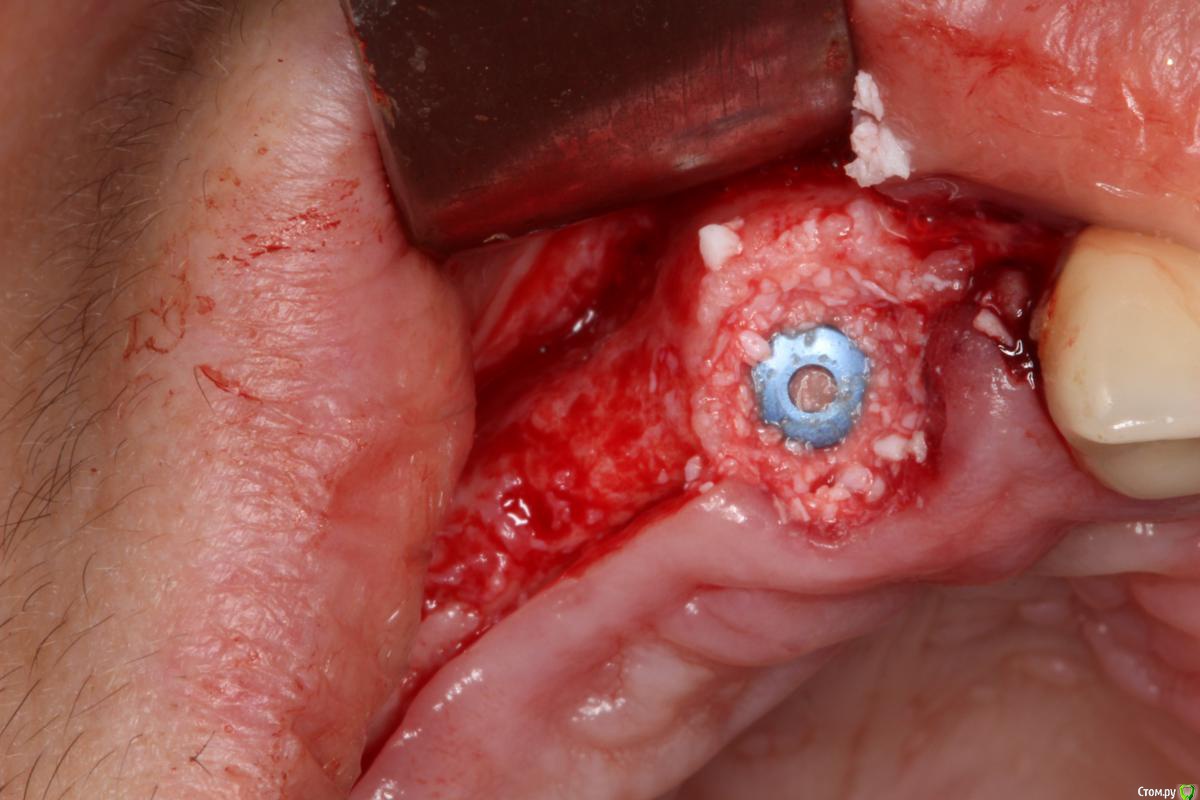

Robinbobin Опубликовано 9 сентября, 2015 Поделиться Опубликовано 9 сентября, 2015 Зуб 1.1 удалил,кюретаж и одномоментно установлен имплантат, заполнил MP3 и закрутил заглушкуУстановил имплантаты в области 1.3,1.4 подсыпал так же MP3 под мембрану и запинилЕсли покажите пальцем на ошибки буду благодарен))) 4 Ссылка на комментарий